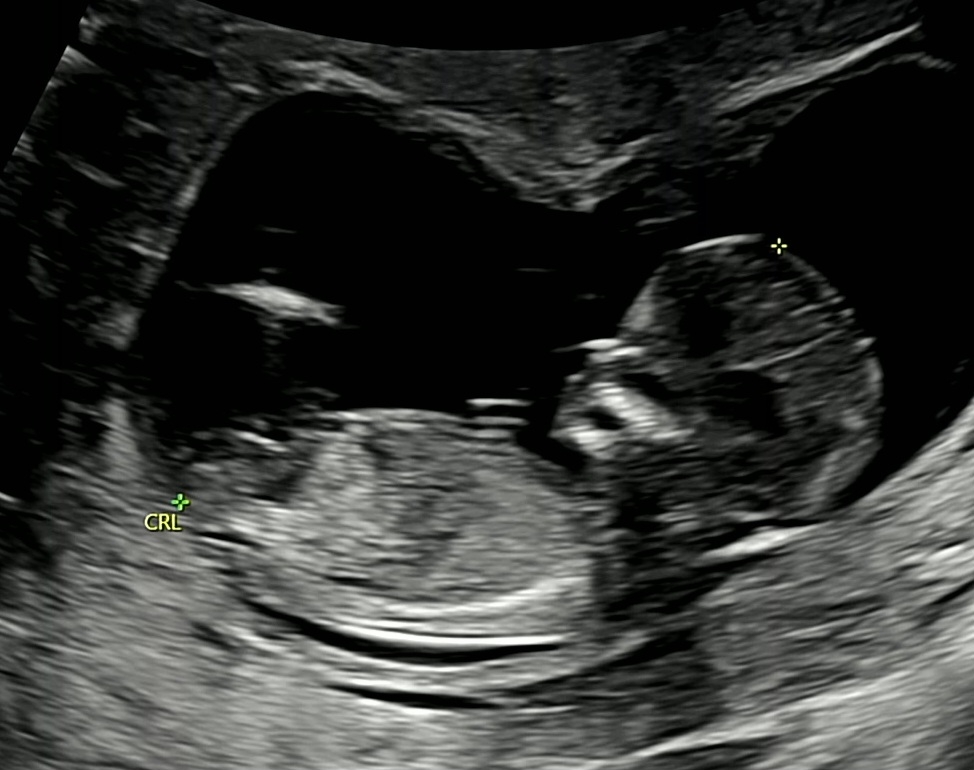

12주 3일차인데 이 사진으로도 예측이 될까요🥹 한달만 기다리면 된다지만 너무 궁금해요..!

아들 한표용~

아들같아요~

생식기부분이 제대로 안보이는데 아들같아요